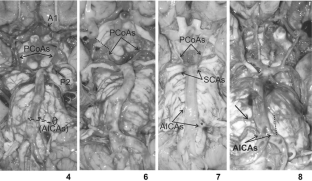

Fig. 1

Fig. 2

Fig. 3

Fig. 4

Fig. 5

Fig. 6

Fig. 7

Fig. 8